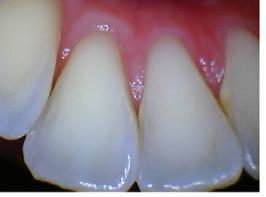

Dental hygienists independently utilize digital scanning for education and motivation. Not only can the clinician educate the patient with the images, but the patient has a visual that is easily understood. These images contain powerful visuals of attrition, fractured teeth, abfraction, gingival recession, overjet, and crowding.4 Biofilm can be displayed after the application of disclosing solution.5 Separate photos are not required to capture the biofilm present when using digital scanning.